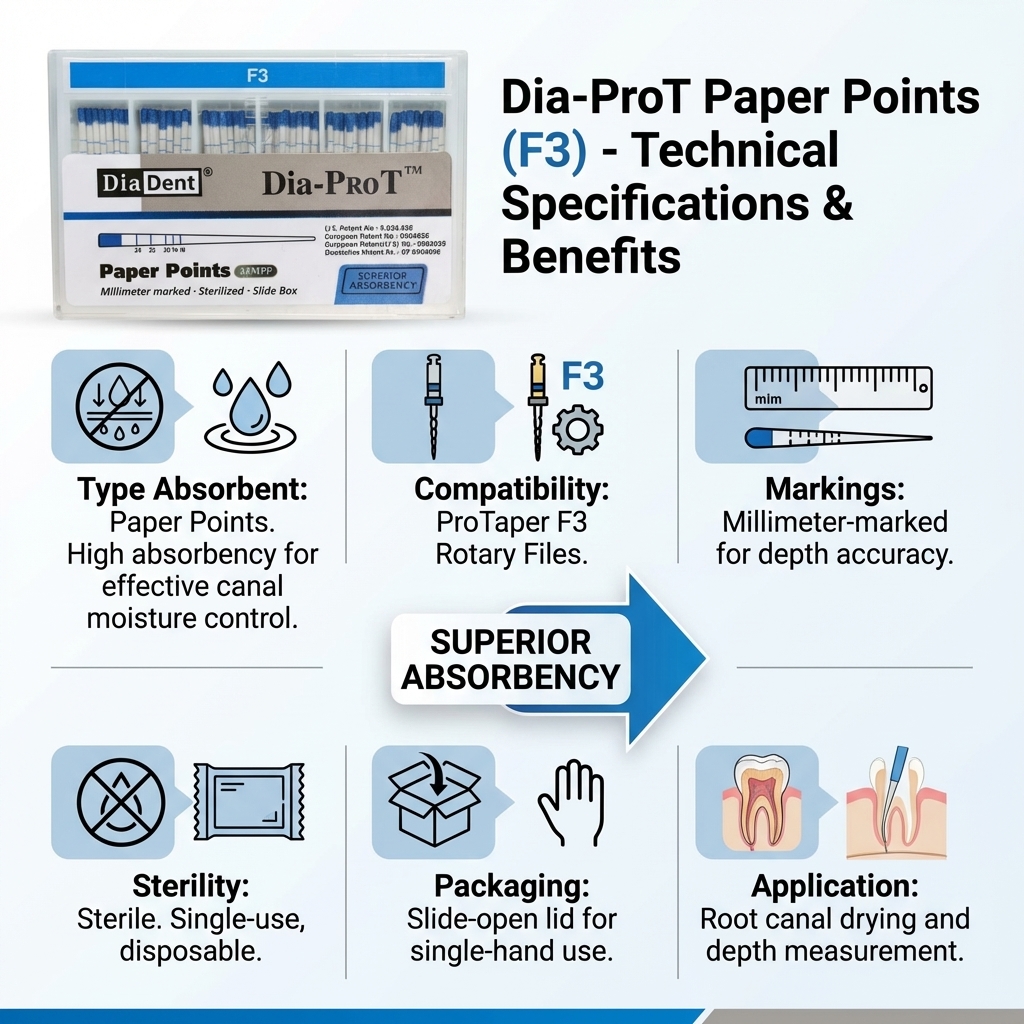

Endodontics: Gutta Percha & Paper Points.